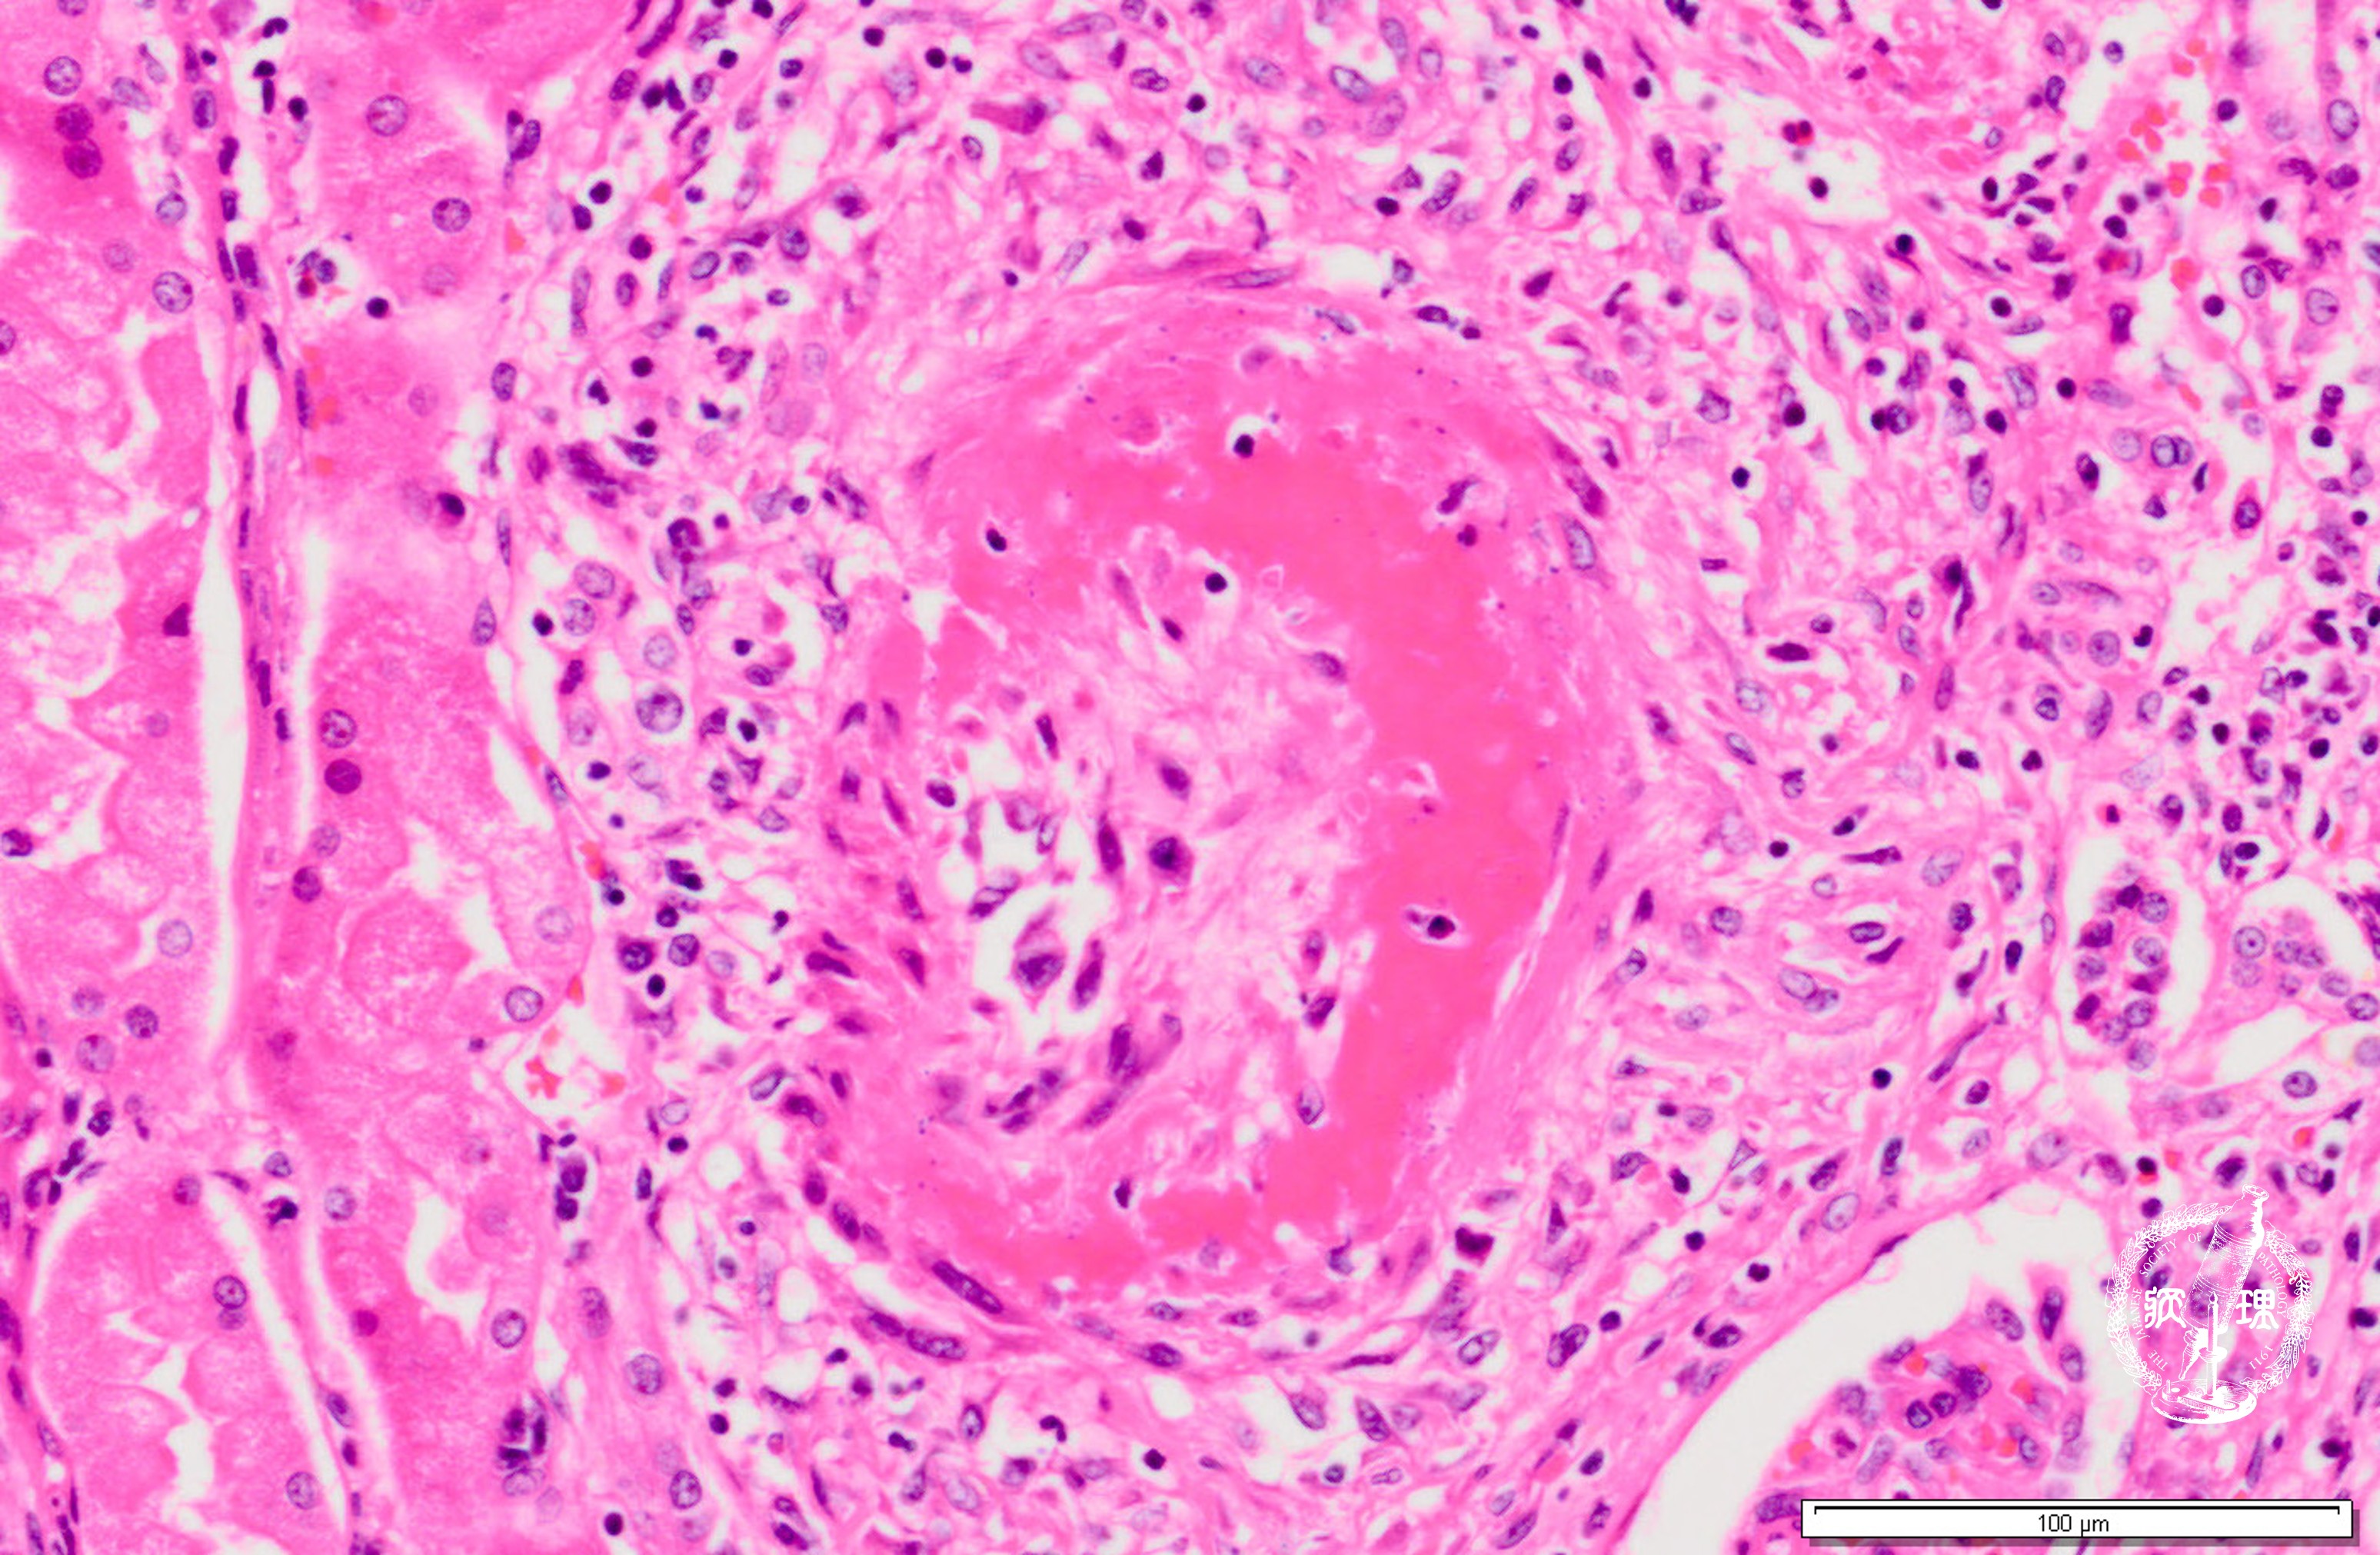

ミクロ像 (HE強拡大): フィブリノイド壊死(矢印)を伴う壊死性血管炎。著明な内膜肥厚(両矢印)を認める。